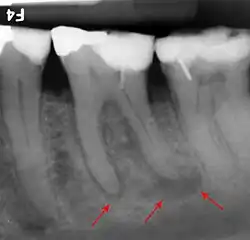

A dental x-ray image (radiograph) showing the shape and number of roots of the molars which cannot be observed in the mouth directly.

Assessment and special investigations

A comprehensive history taking should be performed to find out the pain history of the tooth, the patient's medical history and the history of previous difficult extractions.[2] The tooth should be assessed clinically i.e. checked visually by the dentist.[2] Pre-extraction radiographs are not always necessary but are often taken to confirm the diagnosis and hence appropriate treatment plan.[2] Radiographs also help in visualising the shape and size of roots which are beneficial in planning the extraction.[2] All this information will aid the dentist in foreseeing any difficulties and hence preparing appropriately.[2]